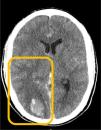

Varón con shock séptico de partes blandas por Streptococcus pyogenes tras traumatismo. Diseminación hematógena con fascitis necrosante en extremidades (resección quirúrgica) y meningitis con absceso cerebral (craniectomía y evacuación). Tomografía (TAC) con contraste: edema en el tejido subcutáneo del brazo izquierdo y en los vientres musculares, y colección en la cara medial de la pierna derecha (fig. 1, flecha azul). Hematoma craneal lobar parietooccipital derecho, edema vasogénico y hemorragia subaracnoidea traumática en cisternas, con aumento del efecto masa (borramiento de surcos y compresión del ventrículo lateral derecho) (fig. 2, recuadro naranja). Resonancia craneal tras empeoramiento clínico (fig. 3): colección occipitotemporal derecha de 3,5×9cm, márgenes irregulares hipercaptantes y restricción (estrellas rojas) sugestiva de absceso cerebral, con pus intraventricular, herniación subfalciana y uncal derecha (flechas rojas), así como hematoma subdural a nivel de la craniectomía (triángulo rojo).